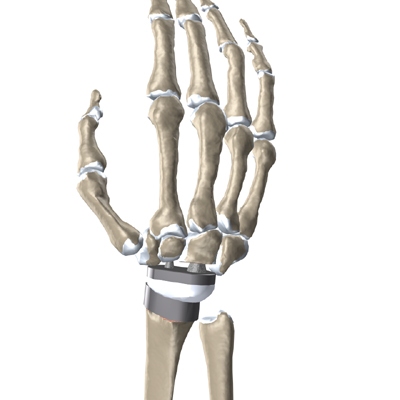

Modern artificial wrist joints are made of metal and plastic. The part that fits against the end of the radius bone of the forearm is called the radial component. It is made up of two pieces. A flat metal piece is placed on the front part of the radius. It has a stem that attaches down into the canal of the bone. A plastic cup fits onto the metal piece, forming a socket for the artificial wrist joint.

The part that replaces the small wrist bones is called the distal component. This piece is made completely of metal. It is globe shaped to fit into the plastic socket on the end of the radius. The metal distal component is attached by two metal stems that fit into the hollow bone marrow cavities of the carpal and metacarpal bones of the hand.

The plastic used in artificial joints is tough and slick. It allows the two pieces of the new joint to glide easily against each other as you move your wrist. The ball and socket allow movement of the wrist in all directions.

Replacement Joint

The surgeon will take some time to get the stems to fit tightly. The joint is put in place and tested through its range of motion to make sure it moves correctly. Once the surgeon is satisfied with the fit, the stems of each metal implant are:

Cemented into Place

The tendons are then placed back into their proper place, and the skin is stitched together.